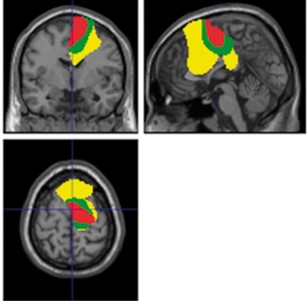

Group data showing significant areas of coupling between subthalamic region and rest of brain superimposed on MRI. Brain regions in yellow are those coupled at beta band (13-30 Hz) frequencies, regions in green are those where coupling is confined to the upper beta band (21-30 Hz), and regions in red are where coupling is suppressed by deep brain stimulation.